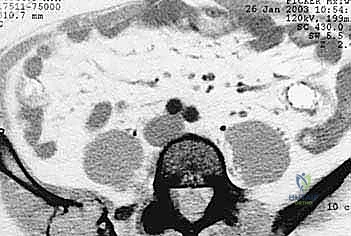

- التصوير المقطعي المحوسب (CT Scan): يقدم صوراً ثلاثية الأبعاد تُظهر بدقة متناهية مدى تدمير القشرة العظمية، وهو الفحص الأهم للتخطيط الجراحي وتحديد خطر حدوث الكسور المرضية.

- التصوير بالرنين المغناطيسي (MRI): الفحص الأفضل لتقييم امتداد الورم خارج العظم إلى الأنسجة الرخوة (العضلات، الأوعية الدموية، الأعصاب) وتقييم مدى إصابة نخاع العظم.

- المسح الذري للعظام (Bone Scan) أو التصوير البوزيتروني (PET-CT): لتحديد ما إذا كان هناك انتشار للسرطان في عظام أخرى من الجسم، ولتقييم النشاط الأيضي للورم.